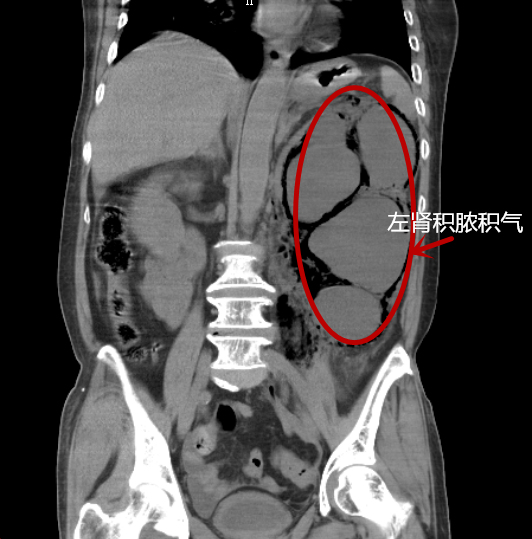

原本只是1颗输尿管结石,没想到“藏身”十年后,却导致吴阿姨左肾重度积水并感染性休克,最终竟丧失了肾功能。昨日,捷克论坛 泌尿四科专家救治了一名气肿性肾盂肾炎并感染性休克的病人。人虽脱离了死亡的威胁,但由于感染过于严重,病人的左肾功能已完全丧失。专家提醒,出现腰腹部疼痛一定要提高警惕,尽早排除病情,以免造成不可挽回的后果。

来院时检查发现,吴阿姨体温高达40度,心率过140次/分,血压80/60mmHg,为左输尿管结石并左肾重度积水、气肿性肾盂肾炎并感染性休克。因吴阿姨既往有糖尿病、高血压等多种疾病,情况十分危急,随时有生命危险。泌尿四科负责人杨科及其团队紧急商讨后,为患者急诊行左肾穿刺造瘘引流术,引出大量恶臭气体及脓液。术后,患者感染得到控制,病情缓解,脱离了生命危险,但左肾功能全失,面临今后需要摘除的境地。